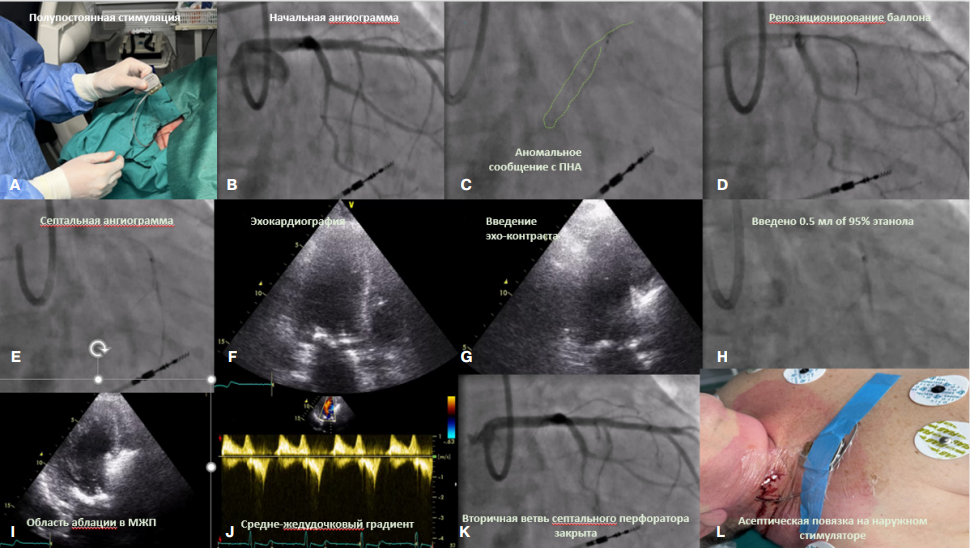

Через пункционный доступ во внутренней яремной вене справа в правый желудочек проведен электрод с активной фиксацией и установлен в межжелудочковую перегородку (МЖП). Инициирована "полупостоянная" стимуляция с частотой 45 в минуту в режиме "по требованию" (рис. 2).

Через доступ в правой лучевой артерии в устье ствола левой коронарной артерии установлен гайд-катетер Eacath Sheathless guide 7.5F PB3.5 (ASAHI Intecc). Выполнена ангиография левой коронарной артерии. Выявлена септальная ветвь (перфоратор), потенциально следующая к целевому фрагменту МЖП соответствующему уровню обструкции. Септальная ветвь катетеризирована проводником Fielder 0.014 inch (ASAHI Intecc). По проводнику в перфоратор заведен коронарный баллон Emerge OTW 1,5*8 мм (Boston Scientific). Баллон раздут до 6 атм. Подтверждена надежная окклюзия септальной ветви. Через просвет баллона введен ЭхоКГ контраст 1 мл (смесь 1/3 гелофузина 4%, 1/3 контраста, 1/3 воздуха). При интраоперационной трансторакальной ЭхоКГ отмечается опалесценция целевого участка МЖП, соответствующая уровню средне-желудочковой обструкции. Толщина МЖП измерена в соответствии с текущими рекомендациями ASE [12]. Через шафт баллонного катетера введено 0,5 мл 95% этанола с последующей экспозицией в течение 5 мин. Получен эффект в виде снижения средне-желудочкового пикового градиента давления с 40 мм рт.ст. до 15 мм рт.ст. Процедура была завершена. Пациентка переведена в палату интенсивной терапии. В послеоперационном периоде и при последующем наблюдении сохранялся синусовый ритм. Через 2 сут. пациентка переведена в общую палату. Послеоперационный период протекал без осложнений, на 8-е сут. пациентка была выписана из стационара.

Рис. 2. Ключевые особенности вмешательства (ЭСА).

Примечание:

А. Установка электрода с активной фиксацией, подключение к наружному постоянному электрокардиостимулятору ("полупостоянная стимуляция").

В. Начальная ангиограмма левой коронарной артерии. Визуализированы потенциальные целевые септальные ветви.

С. При инъекции через раздутый баллон Emerge OTW (over-the-wire balloon) 1,5*8 мм (Boston Scientific) определяется аномальное сообщение данной ветви с передней нисходящей артерией.

D. Выполнено репозиционирование баллона в другую ветвь.

E. Ангиограмма септальной ветви. Аномального сообщения нет.

F-G. Выполнена трансторакальная ЭхоКГ, для эхоконтрастирования введено 1 мл смеси 4% гелофузина с контрастом и воздухом (соотношение 1:1:1). Отмечается четкая зона перфузии, соответствующая уровню обструкции, и не кровоснабжающая нецелевые участки.

Н. Выполнена инъекция 0,5 мл 95% этанола с последующим вытеснением его из шафта баллона небольшой порцией контраста.

I. На ЭхоКГ отмечается область аблации с четкими краями с ЭхоКГ тенью дистальнее зоне воздействия.

J. Отмечается полное устранение градиента ВТЛЖ и остаточный средне-желудочковый градиент давления 9 мм рт.ст.

K. На контрольной ангиограмме отмечается окклюзия вторичной ветви целевой септальной артерии.

L. Наложена асептическая повязка на область наружного постоянного стимулятора.

Сокращения: ВТЛЖ — выносящий тракт левого желудочка, МЖП — межжелудочковая перегородка, ПНА — передняя нисходящая артерия, ЭхоКГ — эхокардиография.